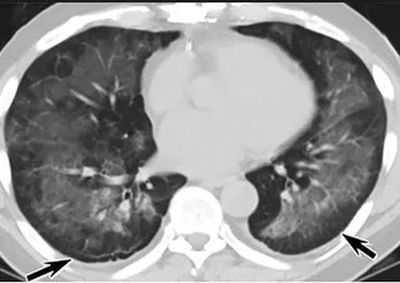

(这4张图,是专家怀疑被误诊为电子烟肺病的其中一个病例的肺片。专家表示,他们不是仅仅通过一张影片做判断的,而是通过这4张涵盖了这名病例肺部多天变化情况的影片进行的研判,认为该病例的病程进展跟新冠更为相似)